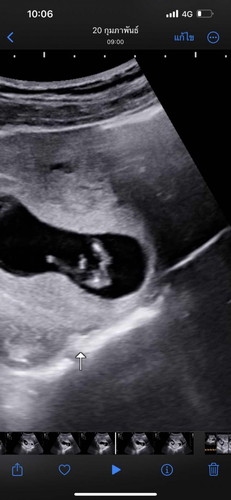

ตอน 12 Weeks ค่ะ แม่พอรู้ไหมค่ะ น้องเป็น ผช. หรือ ผญ. ท้องแรกค่ะ🥰❤️🤰

ยังไม่ชัดค่ะ แต่เดาว่า ผช